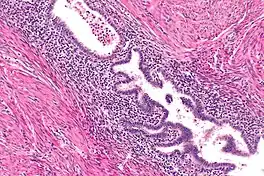

Adenomyomatosis is frequently associated with gallstones and is often diagnosed incidentally, either from a cholecystectomy specimen or autopsy.[4][5][6] No serologic test exists to specify adenomyomatosis and laboratory studies are often normal. Co-existing diseases like cholecystitis may result in abnormal test results, such as elevated levels of white blood cells (leukocytosis), liver enzymes (transaminitis), or bilirubin (hyperbilirubinemia).[5]

Ultrasound is the preferred initial diagnostic choice for suspected gallbladder disease. Several distinct features of adenomyomatosis are discernable using ultrasound, making it a reliable modality for diagnosis.[4][5][6] The most characteristic features seen on ultrasound are the Rokitansky-Aschoff sinuses, which present either as echogenic foci when filled with biliary sludge/gallstones or anechogenic foci when filled with normal bile.[4][5][6] Other key features that may be seen include wall thickening and ring-down artifacts known as "comet tails" (produced by reverberations of sound between the sinuses).[4][5][6] Ultrasound can also distinguish between diffuse, segmental, and localized variants of adenomyomatosis based on morphology.[5][6]

In some cases, gallbladder wall thickening may be seen on ultrasound but is poorly defined and lacking specificity, particularly if the characteristic Rokitansky-Aschoff sinuses are not visualized. This can make it difficult to distinguish adenomyomatosis from other conditions that result in gallbladder wall thickening such as gallbladder cancer.[4][5][6] In these cases, MRI can prove helpful in providing the resolution needed for diagnosis. Especially effective is the T2-weighted MRI at visualizing the pathognomonic Rokitansky-Aschoff sinuses, which appear as round-shaped hyperintense cystic spaces that align in a curvilinear fashion along the gallbladder wall in a pattern described as the ”pearl necklace sign”.[4][5][6]